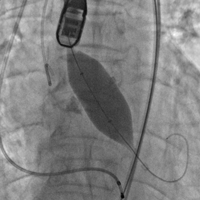

上午11时许,手术直播开始。手术经股动脉入路,使用23#预扩球囊进行跨瓣预扩,预扩后患者突发室颤,血压下降,考虑与患者心功能较差,预扩后反流增加有关。手术团队具有丰富经验,临危不乱,立即予患者电复律、心肺复苏,同时迅速为患者植入一枚25#Renatus介入主动脉瓣,以保证患者左心室-主动脉单向血流。瓣膜植入后,予以补液、血管活性药物治疗,患者血流动力学逐渐稳定,生命体征恢复平稳,术后超声及造影示:瓣膜位置理想,无瓣中返流及瓣周漏,TEE提示主动脉瓣平均跨瓣压差由术前38mmHg降至5mmHg,峰值流速由术前4.3m/s降至1.8m/s。整个手术在一小时内结束,最终获得成功。

球囊预扩 瓣膜释放